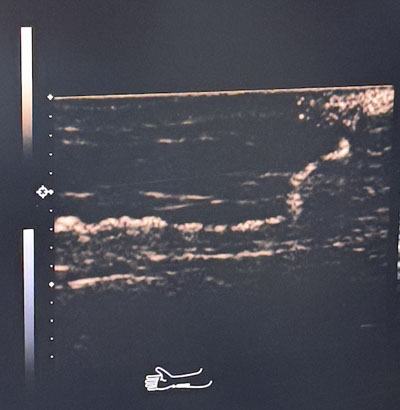

术前超声造影